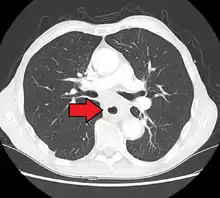

Esophageal cancer (lower part) as a result of Barrettʼs esophagus

Male predominance is particularly strong in this type of esophageal cancer, which occurs about 7 to 10 times more frequently in men.[25] This imbalance may be related to the characteristics and interactions of other known risk factors, including acid reflux and obesity.[25]

The long-term erosive effects of acid reflux (an extremely common condition, also known as gastroesophageal reflux disease or GERD) have been strongly linked to this type of cancer.[26] Longstanding GERD can induce a change of cell type in the lower portion of the esophagus in response to erosion of its squamous lining.[26] This phenomenon, known as Barrett's esophagus, seems to appear about 20 years later in women than in men, possibly due to hormonal factors.[26] Having symptomatic GERD or bile reflux makes Barrett's esophagus more likely, which in turn raises the risk of further changes that can ultimately lead to adenocarcinoma.[16] The risk of developing adenocarcinoma in the presence of Barrett's esophagus is unclear, and may in the past have been overestimated.[2]